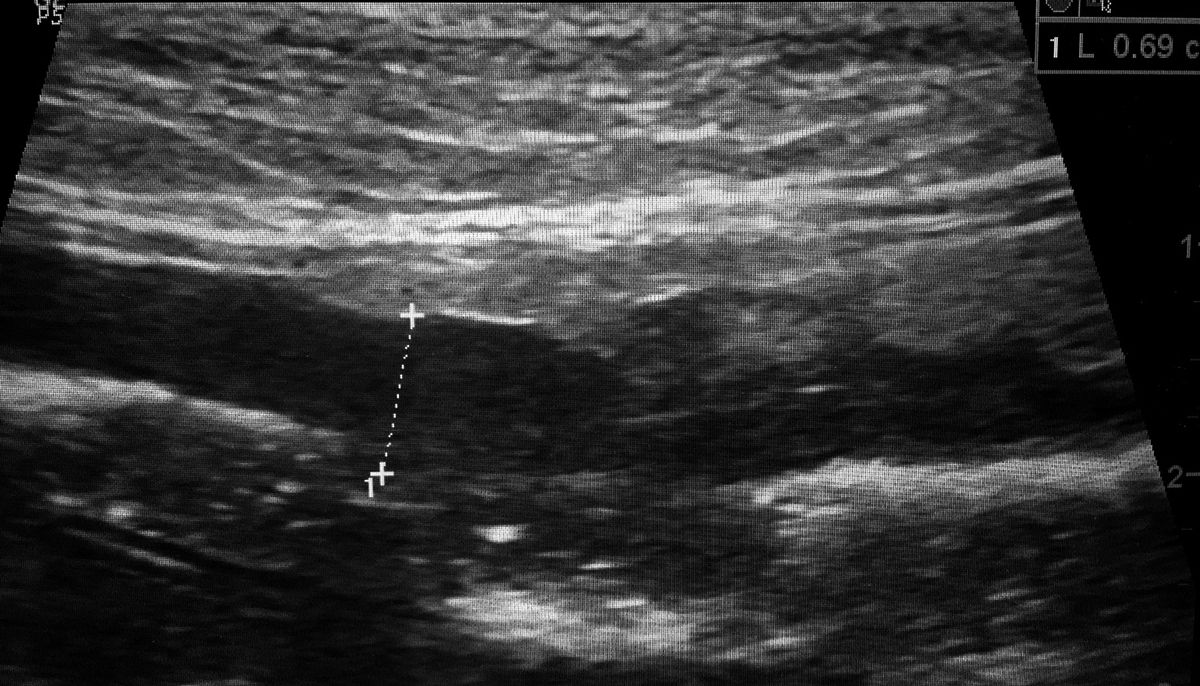

Ультразвукове зображення значно збільшеної петлі тонкої кишки в поздовжній проекції, товщина кишки становить 0,69 см (між мітками) за повної втрати нормальних морфологічних ознак. Пацієнту поставили діагноз ДКЛС

Рис. 3. Ультразвукове зображення значно збільшеної петлі тонкої кишки в поздовжній проекції, товщина кишки становить 0,69 см (між мітками) за повної втрати нормальних морфологічних ознак. Пацієнту поставили діагноз ДКЛС© S. Al-Ghazlat & C. Eriksson de Rezende